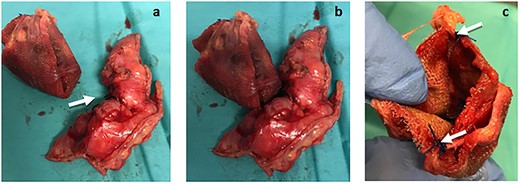

An exploratory midline laparotomy was performed. It revealed a 2 cm cecum perforation caused by direct contact with the polypropylene plug (Fig. 2a–c), which had an intra-peritoneal position at the entrance of the internal inguinal orifice—still with two fixation sutures (previously described as polypropylene). No intraperitoneal collections or bowel compromise were observed.

(a) The plug removed from the peritoneal cavity (left) and the cecum atypical resection specimen (right), where the 2 cm perforation area can be seen (arrows). (b) Plug and cecum positioned according to its intra-operatory location, in which the erosion of the cecum wall was observed in direct contact with the plug. (c) Plug still with two fixation points (arrows).